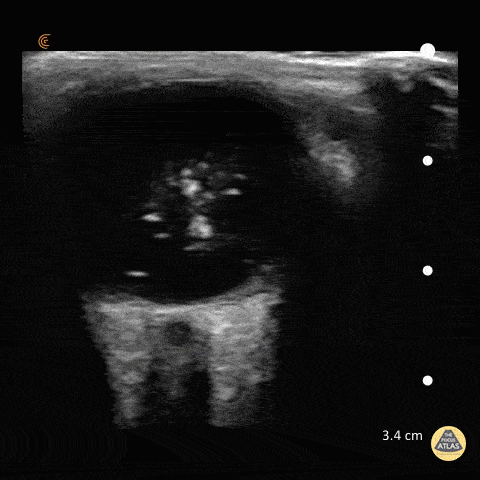

Orbital - Vitreous Hemorrhage - Washing Machine Sign

47 y/o M with coronary artery disease on aspirin/clopidogrel with 4 days of decreased vision in his right eye. POCUS demonstrates swirling, amorphous echogenicities known as "the washing machine sign." If the eye remains still the blood will settle with gravity. Fundoscopic evaluation by ophthalmology confirmed the diagnosis of vitreous hemorrhage. Dr. Matthew Riscinti and Dr. Taylor Conrad - Kings County/SUNY Downstate Emergency Medicine